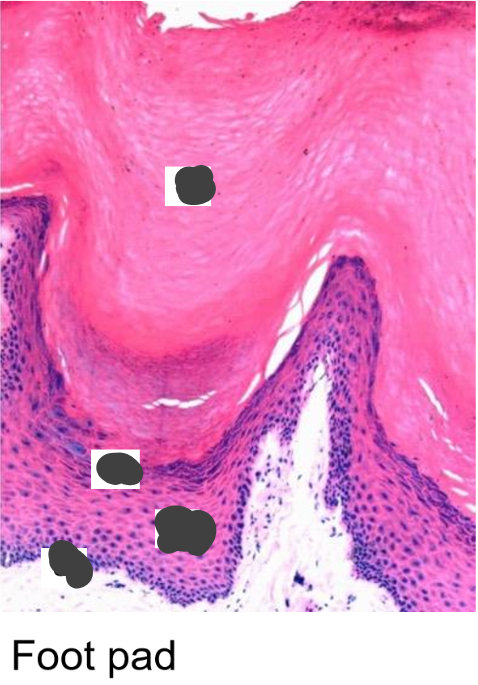

Give an example of a condition relating to keratin in the skin

Palmopalmar hyperkeratosis - genetic defect, causes splitting and pain in the epidermis of foot pads